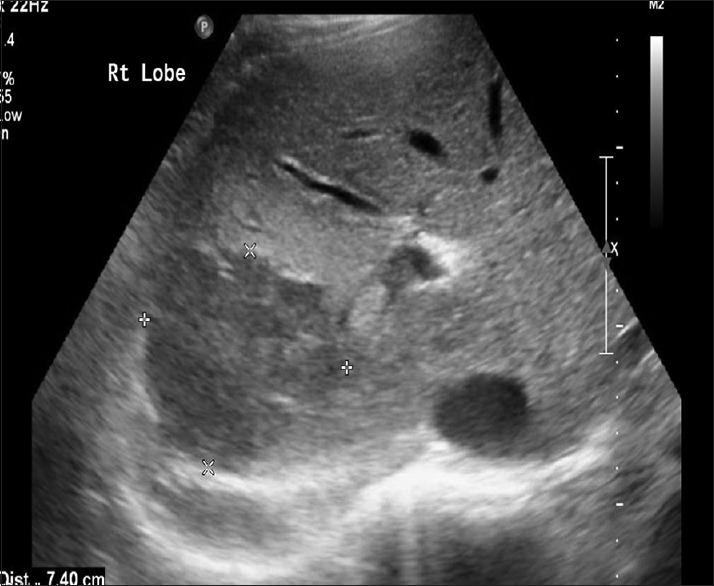

Alhawassi Sami

Department of Surgery, Assistant Consultant in General Surgery, Prince Mohammed bin Abdulaziz Hospital, Riyadh, Kingdom of Saudi Arabia.

Saudi J Med Med Sci. 2017 May-Aug;5(2):189-191. doi: 10.4103/1658-631X.204872. Epub 2017 Apr 20.